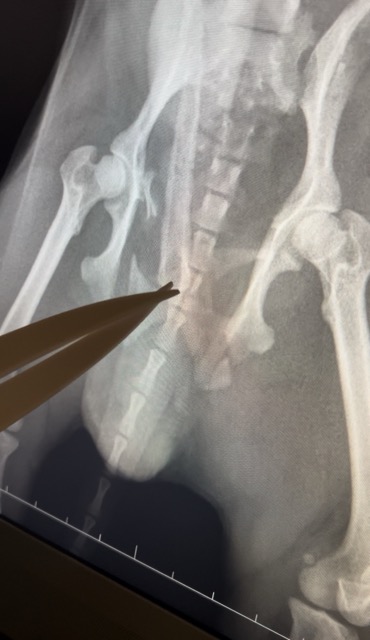

Percuté par une voiture, il a eu le bassin et le tibia fracturés. Hospitalisé, opéré, il a une broche à la cuisse, il se remet de ses blessures.